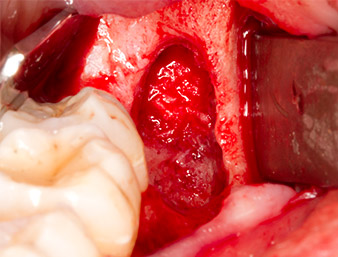

resto radicular 38

Imagen 7: El resto radicular 38 aparece bien representado en su alvéolo para extraerlo a continuación.

A continuación, se utilizó el accesorio P1 para retirar de una pieza el resto radicular de aproximadamente seis milímetros de longitud (figura 11).

El tejido inflamatorio periapical se retiró también con sumo cuidado utilizando un excavador manual. La figura 12 muestra el alvéolo vacío con el nervio alveolar inferior expuesto.

radicular extraído

Imagen 11: El resto radicular extraído medía más de 6 milímetros.